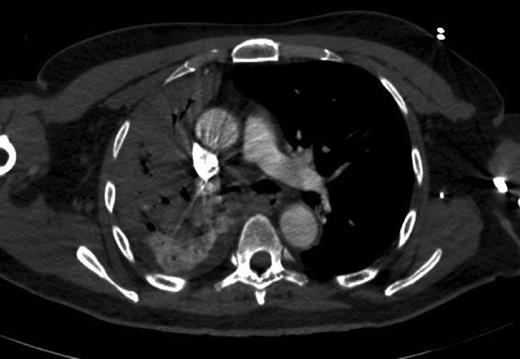

Seventy-two hours after starting his anti-tubercular therapy, he took a turn for the worse and was transferred to the ICU for ventilatory and inotropic support. He had ∼1 l of bleeding per rectum and dropped his haemoglobin (Hb) from 140 to 65 g/l. An oesophagogastroduodenoscopy showed no cause for upper GI bleeding. A CT abdomen + pelvis with contrast was performed, which showed a large (20 cm) inflammatory caecal mass with a moderate amount of intra-abdominal free fluid (Fig. 2). Selective angiography of the superior mesenteric artery demonstrated the bleeding point in the caecum and this was embolized superselectively with coils (Fig. 3).

CT abdomen + pelvis with contrast: large inflammatory caecal mass.